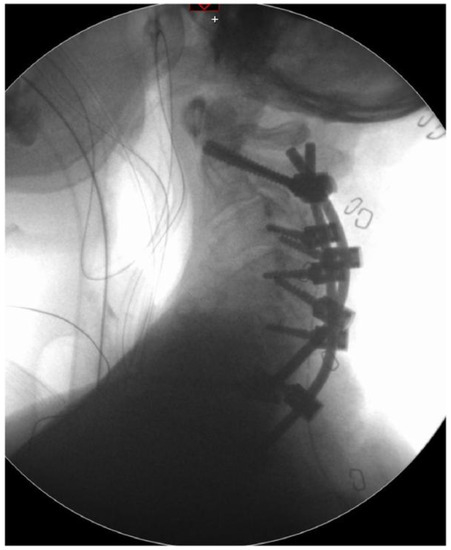

4. Surgical Procedure

5. Follow-Up Control